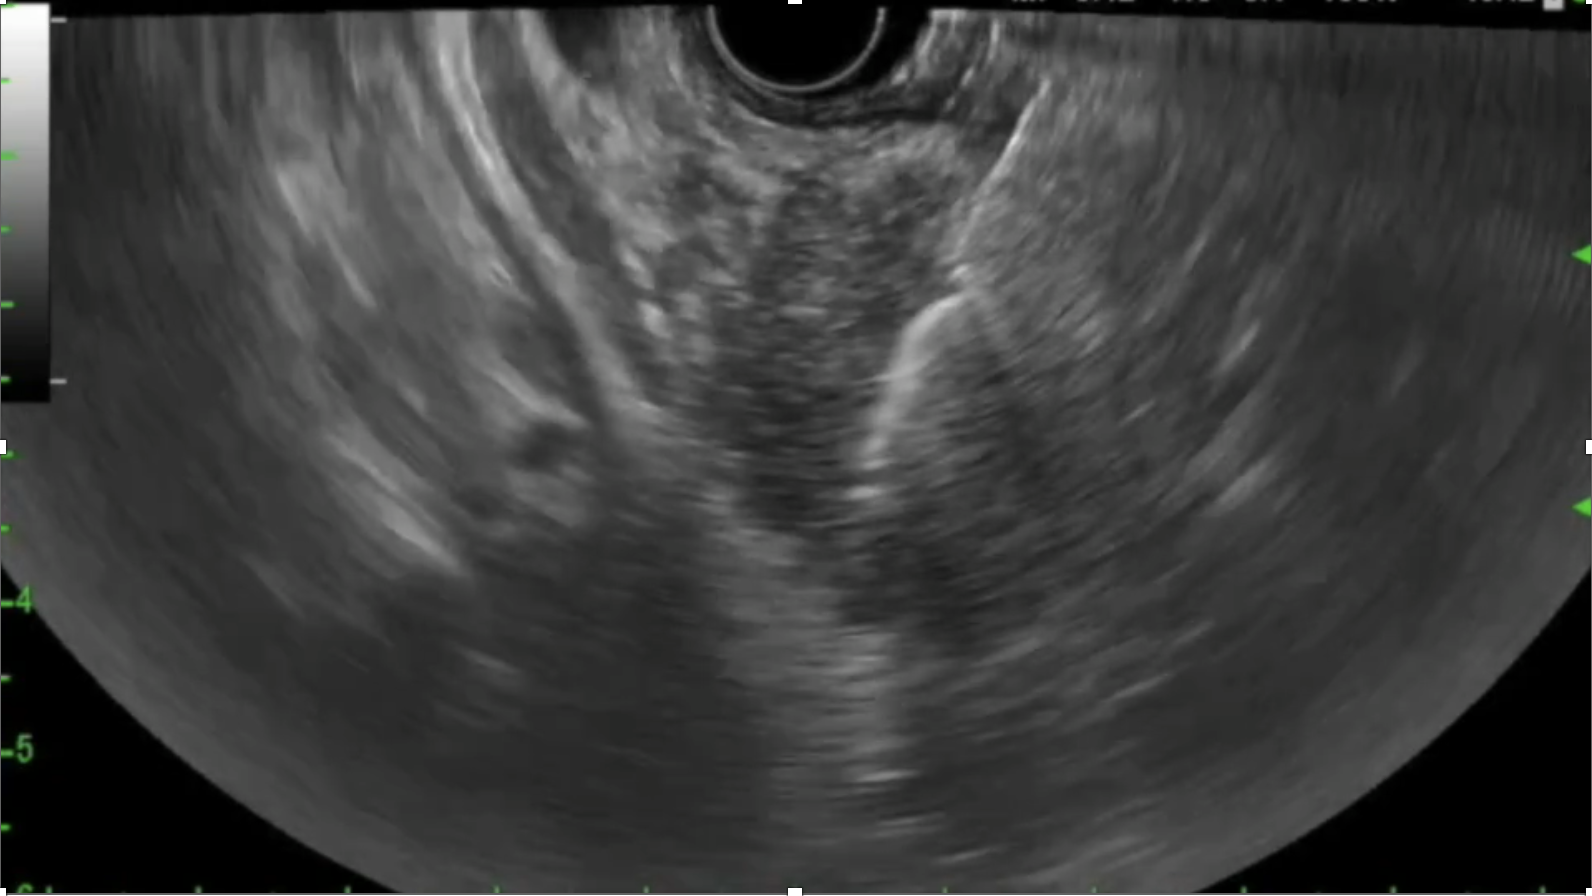

EUS-guided biopsy

2. Endoscopic Ultrasound (EUS)

- Endoscopic ultrasound (EUS) provides high-resolution, real-time imaging of the pancreas and surrounding structures. It is particularly valuable for detecting small or deeply located pancreatic lesions and guiding further diagnostic procedures.

3. Histological Tissue Biopsy (EUS-FNA/B, ERCP sampling)

- Definitive diagnosis remains reliant on pathology examination of tissue samples. EUS guided fine-needle aspiration and biopsies or ERCP-based ductal brushings and biopsies are commonly used.